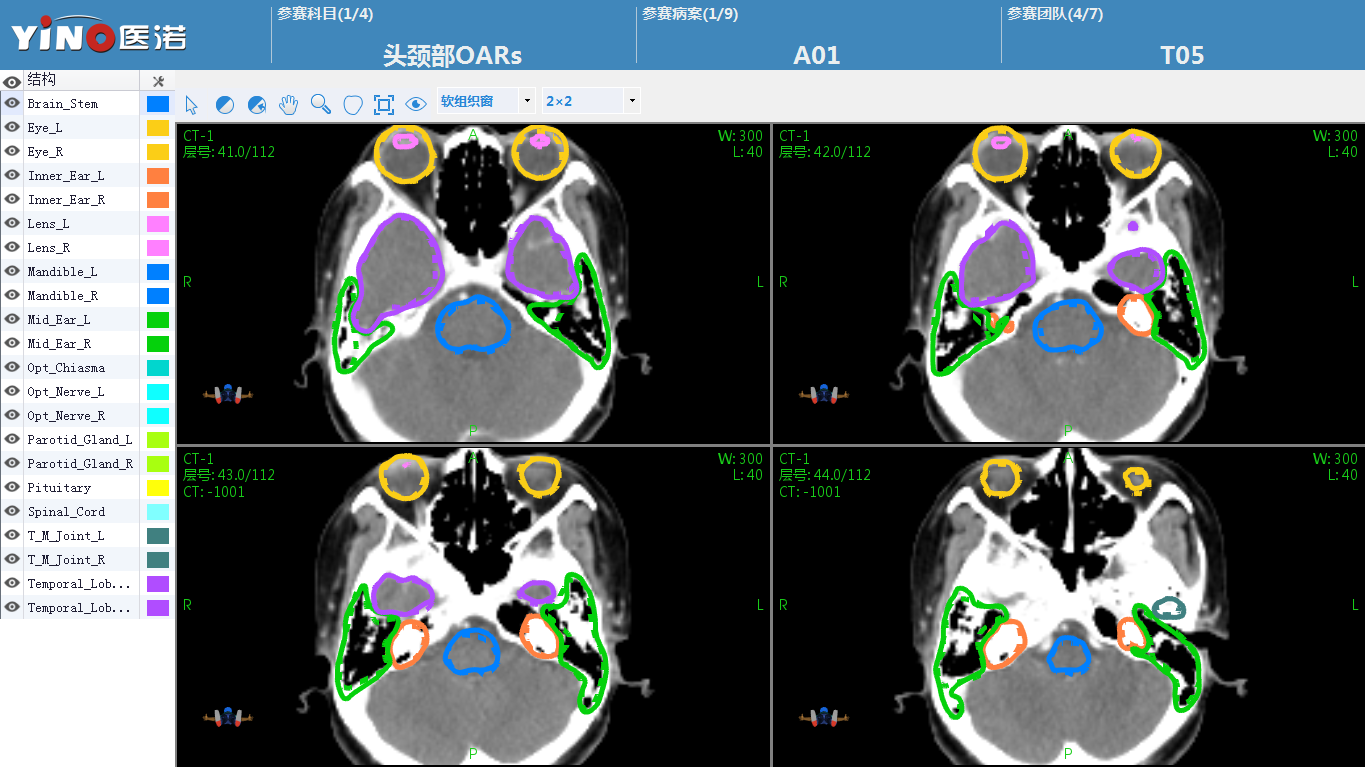

иҝҷдёӨеңәAIеӢҫз”»еӨ§иөӣ���пјҢд»…жҠҘеҗҚеҸӮиөӣеҚ•дҪҚе°ұйқ иҝ‘600дёӘ���пјҢеҠ е…ҘиҜ„еҲҶзҡ„专家дёҺи§Ӯдј—еӨҡиҫҫж•°еҚғдәә�����гҖӮеңЁеӨ§иөӣеҮҶеӨҮеҺҶзЁӢдёӯ���пјҢйңҖиҰҒжҸҗдҫӣеӨ§е®—зҡ„еҲҮеҗҲдёҙеәҠеә”з”Ёж ҮеҮҶ并иғҪз”ЁдәҺAIз®—жі•жЁЎеӯҗи®ӯз»ғе’ҢжөӢиҜ•зҡ„ж•°жҚ®йӣҶ���пјҢд»ҘеҸҠеҲ¶и®ўе®ўи§Ӯе…¬жӯЈзҡ„и§’йҖҗ规еҲҷе’ҢиҜ„еҲҶж ҮеҮҶ�����пјӣеңЁеӨ§иөӣе®ўи§ӮиҜ„еҲҶзҺҜиҠӮ���пјҢйңҖиҰҒдёәжүҖжңүеҸӮиөӣжӯҘйҳҹеӨҡиҫҫж•°еҚғж¬ЎеӢҫз”»ж•ҲжһңжҸҗдәӨдёҫиЎҢд»”з»Ҷе®Ўж ёе’ҢDICEе®ўи§ӮеҲҶеҖјзӣҳз®—�����пјӣеңЁAIеӢҫз”»еӨ§иөӣзҺ°еңә���пјҢиҝҳйңҖиҰҒдёәж•°еҚҒеҗҚиҜ„еҲҶ专家еҸҠж•°зҷҫеҗҚи§ӮиөӣзҫӨдј—жҸҗдҫӣAIеӢҫз”»ж•Ҳжһңеұ•зӨәиҪҜ件е’ҢAIеӢҫз”»жүӢжңәжү“еҲҶзі»з»ҹ�����гҖӮ

дёӨеңәж”ҫз–—AIеӢҫз”»еӨ§иөӣ���пјҢиҷҪ然角йҖҗдҪҝе‘ҪзӣёеҗҢ���пјҢдҪҶеҗ„иҮӘиҮӘеҠӣ�����гҖӮдёӨеңәи§’йҖҗдҪҝз”Ёзҡ„ж•°жҚ®йӣҶе®Ңе…Ёе·®еҲ«���пјҢеҮҶеӨҮеҺҶзЁӢдёӯ���пјҢйңҖиҰҒеҲ’еҲҶдёәдёӨеңәи§’йҖҗеҮҶеӨҮеҗ„иҮӘиҮӘеҠӣзҡ„и®ӯз»ғж•°жҚ®йӣҶе’ҢжөӢиҜ•ж•°жҚ®йӣҶ���пјҢжҖ»з—…дҫӢж•°еҮҢй©ҫ500дҫӢ���пјҢжҙ—жҝҜOARsе’Ңйқ¶еҢәз»“жһ„еҮҢй©ҫ10000дёӘ�����гҖӮ

йңҖиҰҒзү№ж®ҠжҢҮеҮәзҡ„жҳҜ���пјҢCSTROж”ҫз–—AIеӢҫз”»еӨ§иөӣ组委дјҡжҸҗеҮәйқўйўҲOARsгҖҒйј»е’ҪзҷҢGTVгҖҒиғёйғЁOARsгҖҒиӮәзҷҢGTVеӢҫз”»4дёӘи§’йҖҗ科зӣ®йғҪиҰҒеңЁзҺ°еңәдёҫиЎҢAIеӢҫз”»ж•Ҳжһңеұ•зӨә���пјҢ并确дҝқеҗҢж—¶жҜҸдёӘAIеӢҫз”»ж•ҲжһңйғҪиҰҒе’Ң专家еӢҫз”»зҡ„йҮ‘ж ҮеҮҶдёҫиЎҢеҸ еҠ жҜ”з…§жҳҫзӨә���пјҢиҝҷе°ұиҰҒжұӮhjc888й»„йҮ‘еҹҺжҸҗдҫӣзҡ„жүӢиүәж•ҲеҠіе№іеҸ°йңҖиҰҒеҢ…з®Ўиҝ‘500дҫӢз—…дҫӢпјҲжҜҸдёӘз—…дҫӢеҢ…жӢ¬100еӨҡеј CTеӣҫеғҸе’ҢеӨ§е®—зҡ„з»“жһ„иҪ®е»“зәҝе…ұи®Ў50000еј CTеҪұеғҸзӯүе®Ңж•ҙзҡ„з—…дҫӢдҝЎжҒҜпјүиҰҒеҗҢж—¶еңЁе№іеҸ°дёҠе®һж—¶еҗҢжӯҘйЎәз•…иҝҗиЎҢ�����гҖӮдҪңдёәжҳҫи‘—жҜ”з…§зҡ„жҳҜ���пјҢзҺ°еңЁеңЁеҗ„еҢ»йҷўж”ҫз–—дёӯеҝғе№іж—¶дҪҝз”Ёзҡ„еҢ»з”ҹдәӢжғ…з«ҷжҲ–жІ»з–—еҰ„жғізі»з»ҹпјҲTPSпјүжқҘеұ•зӨәеӢҫз”»ж•Ҳжһң���пјҢдёҖж¬ЎеҸӘиғҪзҝ»ејҖдёҖдҫӢз—…жЎҲ���пјҢдёҖж ·е№іеёёзҡ„еҢ»з”ҹдәӢжғ…з«ҷзҝ»ејҖдёҖдёӘз—…дҫӢйҖҡеёёйғҪйңҖиҰҒеҮ еҚҒз§’жүҚеҚҺеңЁиҪҜ件з•ҢйқўжҳҫзӨәеҮәжқҘ�����гҖӮhjc888й»„йҮ‘еҹҺдҫқжүҳеңЁж·ұиҖ•ж”ҫз–—еҚҒдә”е№ҙзҡ„жүӢиүәз§ҜзҙҜдёҺдә§е“ҒдјҳеҠҝ���пјҢжү“йҖ дәҶеҸҜе®№зәіеӨҡ家зӣёеҠ©еҢ»йҷўдёҺ专家еҗҢж—¶еңЁзәҝжҸҗдҫӣиҝңзЁӢж”ҫз–—еҚҸдҪңзҡ„жүӢиүәж•ҲеҠіе№іеҸ°���пјҢеҫҲеҘҪзҡ„зҹҘи¶ідәҶжң¬ж¬ЎеӨ§иөӣзҡ„иҰҒжұӮ���пјҢеҸҜд»ҘдёҖж¬ЎжҖ§еҝ«йҖҹзҝ»ејҖ500дҫӢеҢ…жӢ¬еҮҢй©ҫ5дёҮеј й«ҳжё…CTеҪұеғҸж•°жҚ®зҡ„еӢҫз”»з—…жЎҲ���пјҢ并иғҪеӨҹзҹҘи¶іеҮ еҚҒеҗҚ专家еҗҢж—¶еңЁ500дҫӢAIеӢҫз”»ж•Ҳжһңд№Ӣй—ҙдёҫиЎҢжҒЈж„ҸеҫҖиҝ”еҲҮжҚў���пјҢжҜҸж¬ЎеҲҮжҚўз—…жЎҲеқҮдёҚеҲ°1з§’ж—¶й—ҙеҚіеҸҜйЎәз•…е®ҢжҲҗ�����гҖӮ